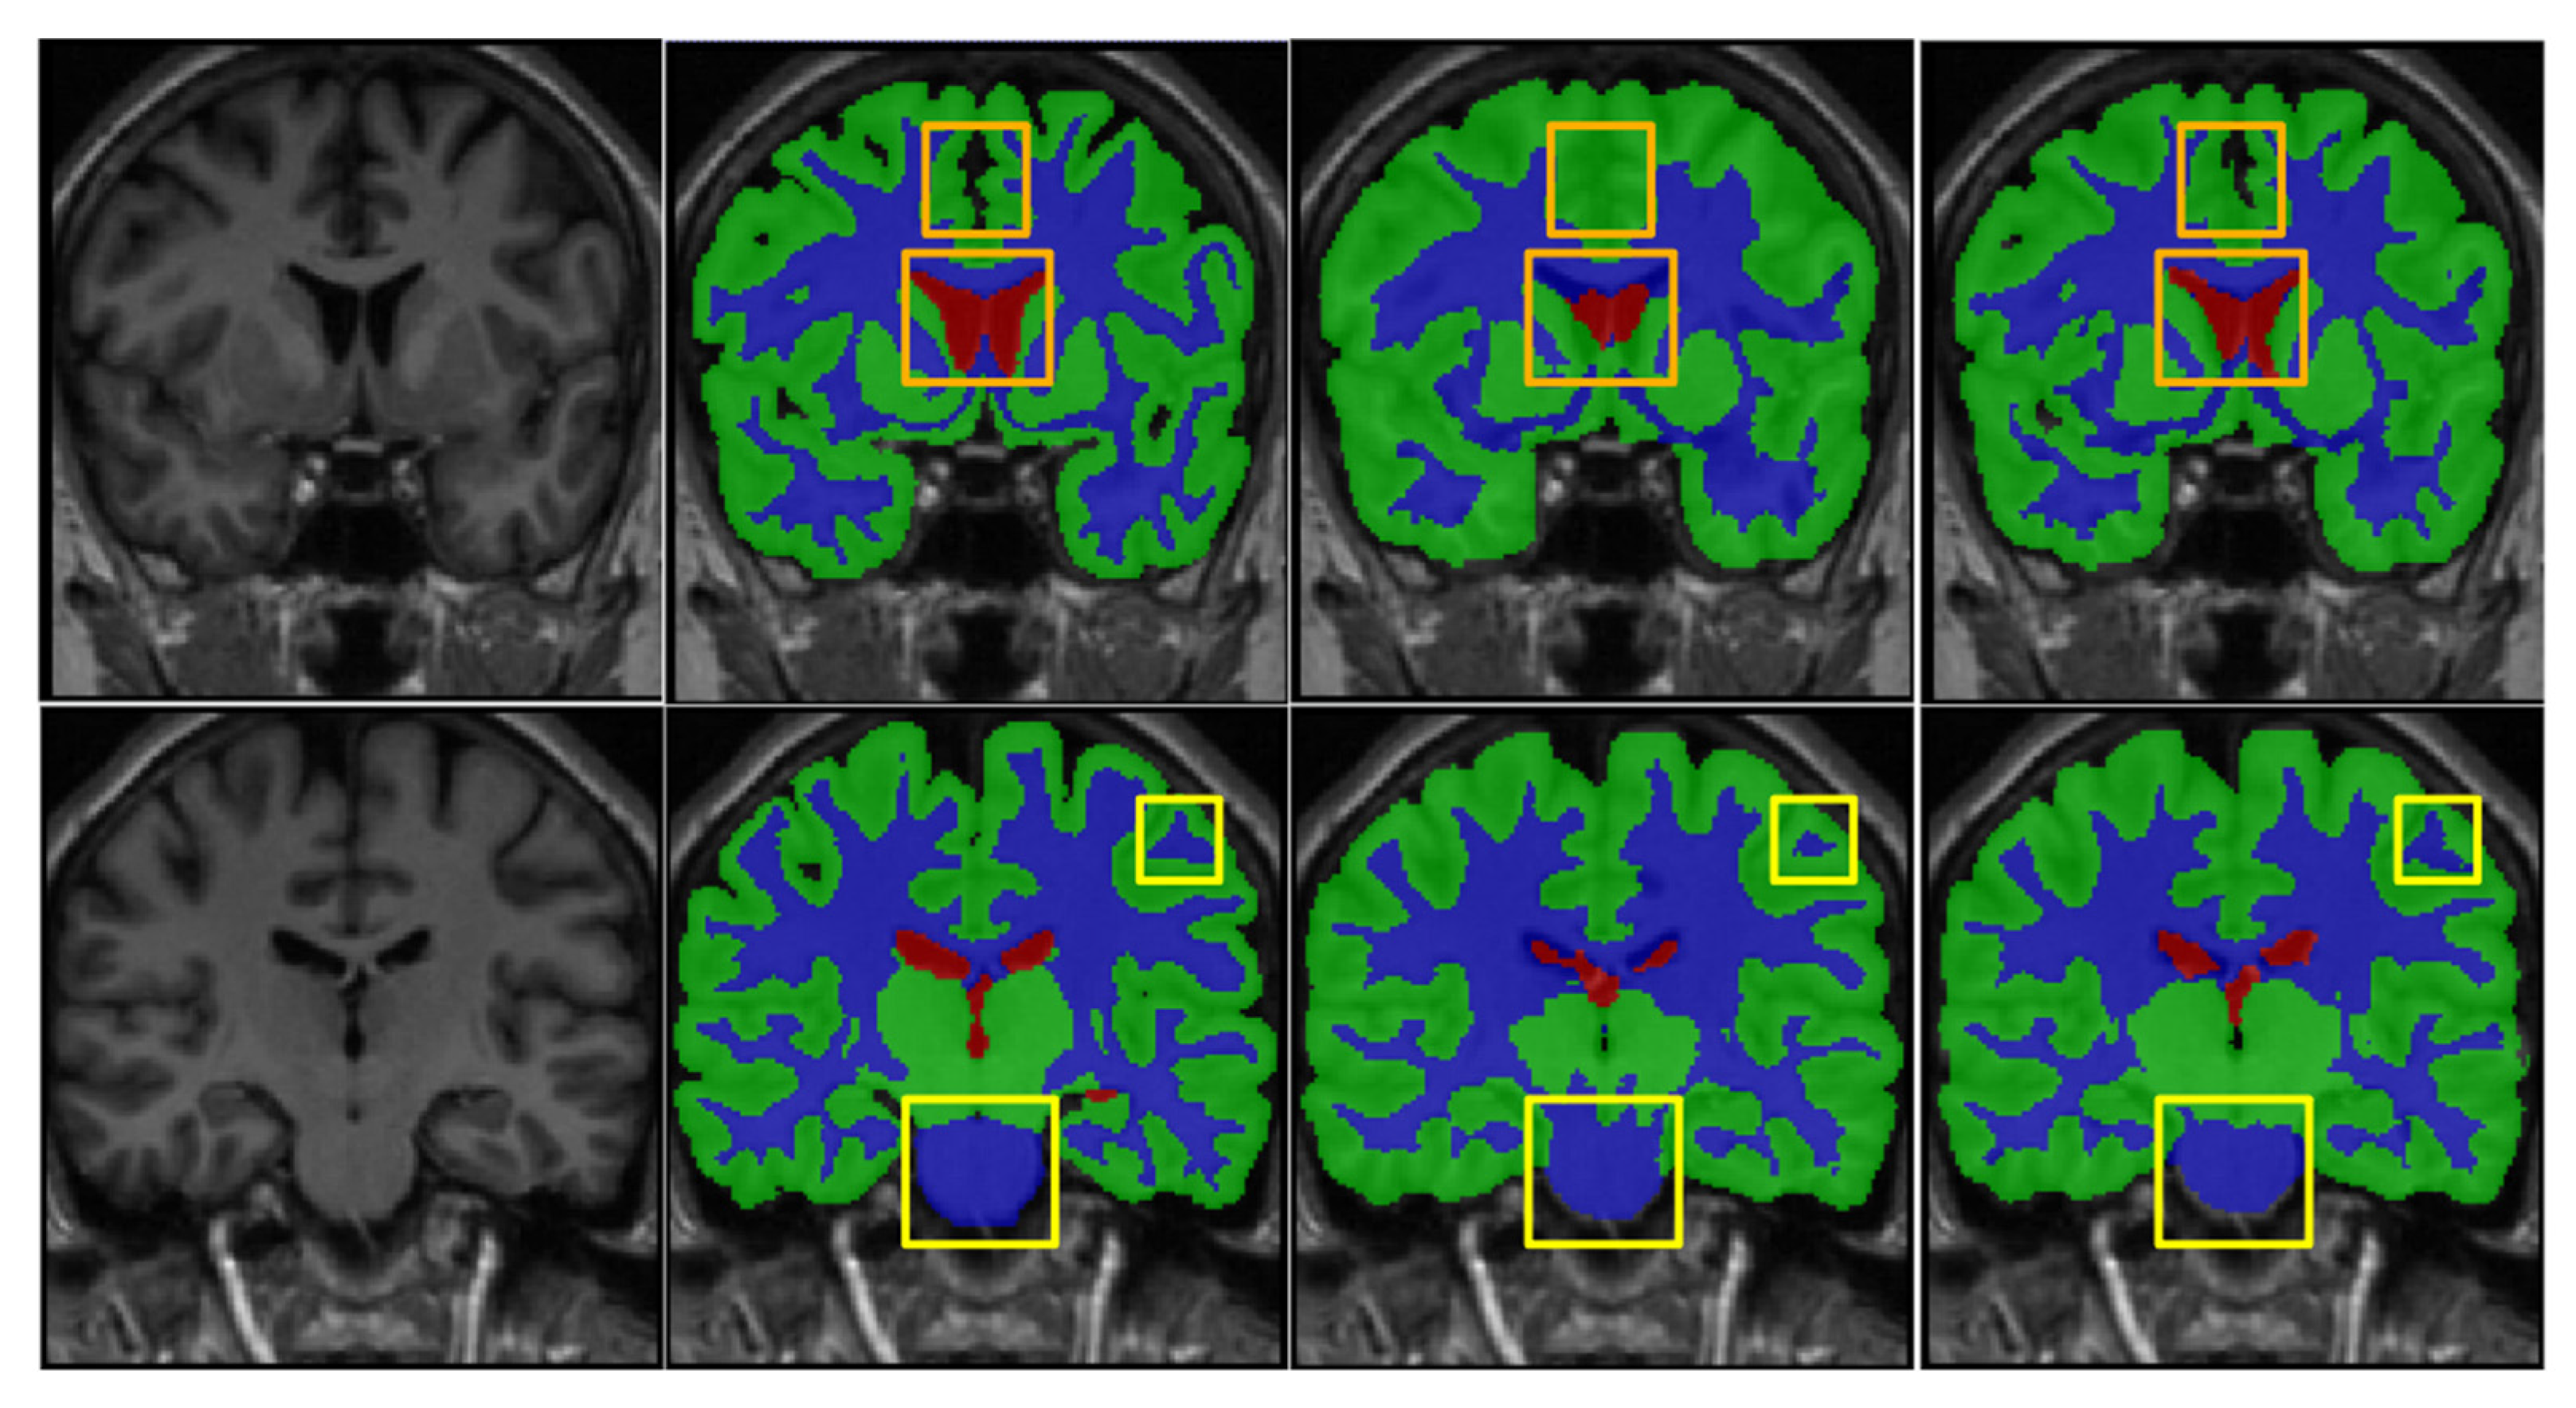

4.3. Comparison with Existing State-of-the-Art Methods